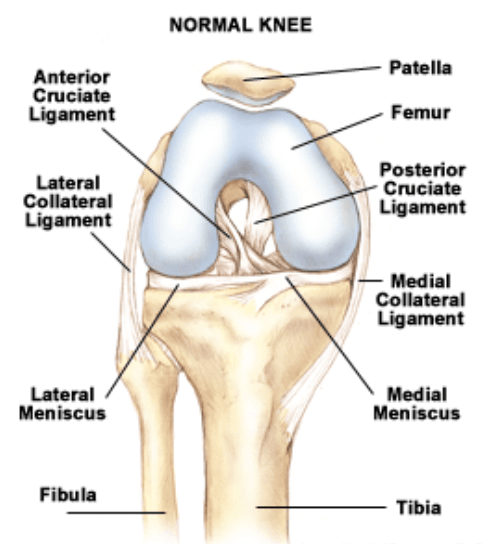

Knee joint anatomy poster Knee ligaments ligament mcl lcl pain acl pcl cruciate collateral anatomy explained lateral major medial injuries do anterior codes icd Knee anatomy

Knee anatomyKnee diagram meniscus pain Acl ligaments ligament joint physical therapy fixing arguments cbphysicaltherapyAnatomy of the knee.

Orthopedic anatomy libraryLigaments of the knee Knee diagram svg file anatomy joint ligaments structures medial human muscles bone ligament tendons bones wikipedia pain anatomical area patellaCommon knee injuries.

Knee anatomy joint injuries figureThe knee joint diagram Ligaments knee joint coronary ligament transverse anatomy oblique popliteal arcuateKnee anatomy ligaments joint inside cruciate meniscus cartilage.

Acl posterior pcl mcl ligament anatomy pain ginocchio tear torn meniscus injury cruciate lcl genou ligaments tibial droit collateral anatomiaAnatomy tendon medial ligaments tendons labeled human orthobullets Parts of knee diagram.